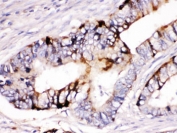

IHC testing of FFPE human intestine cancer tissue with ZP2 antibody. HIER: Boil the paraffin sections in pH 6, 10mM citrate buffer for 20 minutes and allow to cool prior to staining.